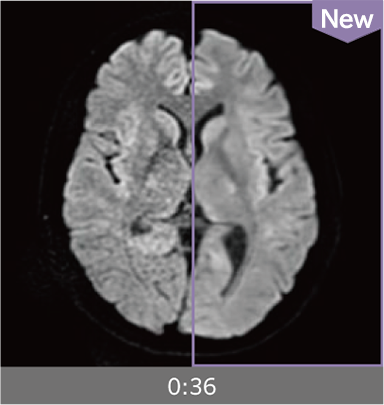

Images can be obtained at high speed by combining two technologies: IP-RAPID, which reduces imaging time while maintaining image quality, and Advanced Reconstruction to improve image quality.

Under-sampling reduces imaging time, and iterative reconstruction with IP-RAPID reduces noise and artifacts.

In addition, Advanced Reconstruction further eliminates noise and produces images that are easier to use in making a diagnosis.